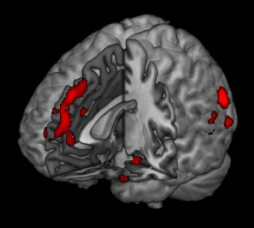

Functional neuroimages look at the activity of the brain, how it’s working. A common approach to functional neuroimaging is to compare an individual’s brain function to norms to discover regions of abnormal functioning. This enables us to see where the brain is either failing or functioning better than average. Here’s an example of a functional MRI (fMRI) superimposed on a structural MRI to illustrate specific brain region activity.